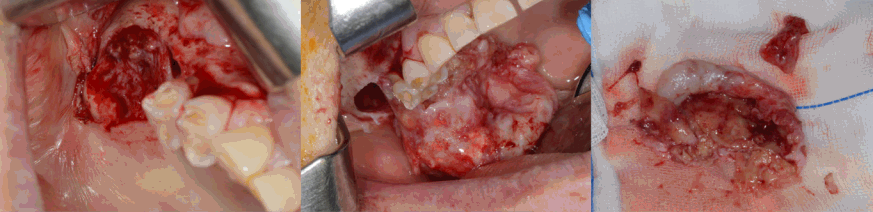

이 증례보고는 조선대학교치과병원 기관생명윤리위원회에서 승인 번호 CUDHIRB 2401 003으로 승인을 받았다. 72세의 여자 환자가 1년 전 우측 상악 제1,2 대구치 발거 후, 수개월 동안 지속해서 해당 부위에서 염증 삼출물이 나온다는 증상을 호소로 조선대학교 치과병원에 내원하였다. 처음 내원했을 때, 양측 상악 제1, 2대구치(#16,17,26,27)는 결손된 상태였고 임상 검사에서 발치 후 치유가 완전하게 진행된 정상 구강 점막의 형태를 관찰할 수 있었다. 환자는 전신 질환으로 고혈압과 당뇨가 있었으며, 안면부 외상이나 상악동 수술 등의 병력은 존재하지 않았다.파노라마방사선영상에서 우측 상악동 내부 대부분의 공간이 방사선불투과상으로 채워져 있는 것을 관찰할 수 있었다(Fig. 1). 또한 반대측과 비교하였을 때 우측 상악동 저의 경계가 분명하지 않고 치조골의 골밀도가 감소된 소견을 보였다. 추가적인 평가를 위해 cone-beam computed tomography(CBCT)에서 얻어진 영상을 axial, coronal, panoramic plane으로 재구성하였다. 재구성된 영상에서 우측 상악동 내부를 채우고 있는 장경 3.5 cm정도의 낭종 병소가 관찰되었으며, 상악동의 전방 및 후외측 골이 팽융되고 상악동의 후외측 경계와 상악 치조골이 병소에 의해 소실된 소견이었다(Fig. 2). 병소의 경계는 대체적으로 잘 구분되고 타원 형태의 구조를 보였다. 경계 부위에서는 비후된 형태의 경화성 골 변연이 관찰되었고 병소 내부에서는 불규칙하고 무정형의 석회화가 산재되어 있었다. 술후상악낭(postoperative maxillary cyst)과 석회화치성낭(calcifying odontogenic cyst)을 감별진단으로 고려하였다.본원 구강악안면외과에서 전신마취 하 구강 내 치조정측 접근을 통한 수술적 적출을 시행하였는데, 수술하면서 우측 상악동에서 농이 배출되는 양상과 육안상으로 볼 때 육아종처럼 보여지는 종괴(granulative mass)를 관찰할 수 있었다(Fig. 3). 수술 후 병리조직학적 검사 결과, 광범위한 골화를 동반한 콜레스테롤 육아종(cholesterol granuloma with massive ossification)으로 진단되었다(Fig. 4).환자는 수술 후 약 2주 정도 수술 부위에 대한 관리와 상악동의 배농 및 환기 상태의 유지를 위해 추가적인 처치를 받은 후 퇴원하였고, 수술 8개월 후 시행한 CBCT 검사에서 재발과 관련된 소견이 관찰되지 않았으며(Fig. 5) 현재까지 별다른 합병증 없이 추적 관찰 중이다.